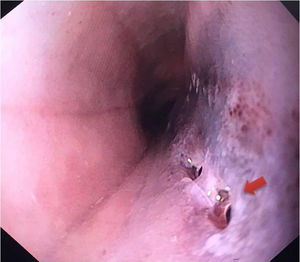

A 20-year-old man presented with chest pain and fever. Computed tomography of the chest showed a fusiform paravertebral mass measuring 27 × 30 × 100 mm indicative of a superinfected collection (Fig. 1). An oesophageal transit study with Gastrografin® ruled out perforation (Fig. 2). A decision was made to administer antibiotic therapy and perform a surgical examination given the evidence of superinfection. Intraoperative oesophagogastroduodenoscopy revealed, 30−36 cm from the dental arch, whitish oesophageal mucosa with haemorrhagic suffusion, a mass effect and two orifices draining a purulent fluid (Fig. 3). Right lateral thoracoscopy revealed thickening of the oesophageal wall, with no evidence of cyst formation. On subsequent imaging tests, the collection was seen to gradually shrink and then disappear. Oesophageal biopsies in follow-up oesophagogastroduodenoscopy yielded no histological findings.

Oesophageal intramural dissection consists of laceration of the mucosa, resulting in longitudinal dissection that separates the mucosa from the submucosa.1,2 In a contained perforation, the muscle layer remains intact.1–3 Microorganisms can breach the lacerated mucosa and complicate the situation with an intramural oesophageal abscess.1 This finding is rare and usually iatrogenic in patients on anticoagulation therapy.1,2 However, we have reported an idiopathic case in a young patient with no history of endoscopic manipulation, vomiting or trauma. Imaging tests may show a double-lumen oesophagus or, as in this case, a hypodense paraoesophageal collection.1